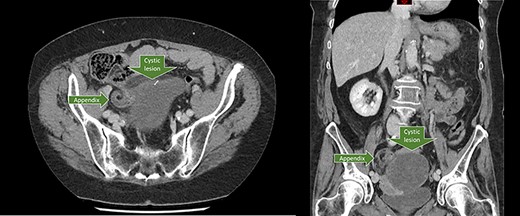

Axial and coronal CT-scan showing the dilated appendix in close proximity to the cystic lesion.

A 66-year old female patient, with a past medical history of hypertension, presented to the emergency department with a central stomach ache radiating to the upper and lower abdomen. Complaints initiated that morning and were continuously present in varying severity. The pain was accompanied by nausea, vomiting and anorexia. The patient had normal vital parameters with a pulse rate of 82 beats per minute and a temperature of 37.4°C. Physical examination of the abdomen showed tenderness in the suprapubic region. Laboratory results were normal except a leukocytosis of 11.2 x 10*9/L [reference 4–10 x 10*9/L]. Urinalysis showed positivity of nitrate, and presence of some leukocytes and erythrocytes. The presumptive diagnosis was an urinary tract infection for which an urine culture was performed, and antibiotics were prescribed. Because of the atypical presentation, the patient was reassessed at the emergency department the following morning. The complaints were persistent and the abdominal examination still showed tenderness in the suprapubic region but at this moment also in the right lower quadrant (RLQ). Laboratory results showed a C-reactive protein (CRP) of 57 mg/L (reference 0–5 mg/L) and a leukocytosis of 13.2 x 10*9/L. A computed tomography was performed and showed a large cystic lesion with wall calcifications in the RLQ measuring 8.6 x 7.1 x 9.6 cm probably originating from the right ovary (Fig. 1). The appendix was situated in close proximity to this abnormality, and measures 6 mm at the base and 1.1 cm more distally, with infiltration of the surrounding intra-abdominal fat. The appendix looked rotated to caudal. One of the differential diagnosis was a torsion of the right ovarium. An additional ultrasound was carried out by the radiologist to try to clarify the anatomical origin of the abnormalities, but was inconclusive. Informed consent was obtained for a diagnostic laparoscopy with a gynecologist standby. During laparoscopy, inspection of the intra-abdominal genitals showed no abnormalities besides a small myoma of the uterus. The appendix showed a large tumor, which was twisted several times at its base and was purple/ischemic discolored (Fig. 2). After complete detorsion, the appendix was stapled with an endostapler and the appendix was retrieved through a Pfannenstiel incision. The patient recovered without any complications and was discharged home the next day. Histopathologic investigation showed a cystic cavity with a calcificated wall filled with mucus and confirmed the diagnosis of low-grade mucinous neoplasm of the appendix, with reactive changes due to the torsion. There were no signs of perforation and the appendix was removed completely. The patient was discharged from follow up after 8 days.